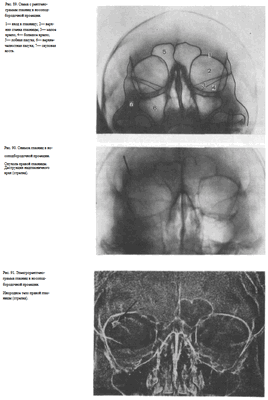

УКЛАДКИ СНИМОК ГЛАЗНИЦЫ В НОСОПОДБОРОДОЧНОЙ ПРОЕКЦИИ

Назначение снимка. Изучение состояния костей, образующих вход в глазницу, костной структуры верхней и наружной ее стенок.

Укладка больного для выполнения снимка сходна с укладкой для выполнения обзорного снимка в этой же проекции. В данном случае используюткассету размером 13X18 см, располагая ее в кассетодержателе в поперечном положении. Больной прилежит к столу подбородком и кончиком носа,переносье соответствует центру кассеты. Центральный пучок излучениянаправляют на центр кассеты. Фокусное расстояние—100 см.

В этой же укладке может быть выполнен снимок одной (правой или левой) глазницы. В таких случаях центр снимаемой глазницы соответствует центру кассеты, и на него отвесно направляют пучок излучения, используя тубус или диафрагмирование пучка излучения с помощью щелевой диафрагмы. Фокусное расстояние—100 см (рис. 88).

Информативность снимка. На снимке хорошо видны вход в глазницу, структура ее стенок, иногда малое и большое крыло клиновидной кости (рис. 89). На снимке в этой проекции могут быть выявлены деструктивные изменения стенок глазницы и инородные тела в ее полости (рис. 90, 91). Для выявления изменений в области верхней стенки глазницы (например, при

диагностике переломов) снимок целесообразно выполнять не в носоподбородочной, а в подбородочной проекции.

На таких снимках верхняя стенка глазницы проекционно искажается в меньшей степени, и все изменения в ее области видны более отчетливо (см. рис. 54, 55).

На прицельном снимке каждой из глазниц в этой же проекции, как правило, небольшие изменения структуры стенок, а также мелкие инородные тела глаза видны лучше. Такие снимки широко используют в офтальмологической практике (рис. 92).

Критерии правильности технических условий съемки и правильности укладки основываются на четкости выявления костной структуры и симметричности изображения глазниц.